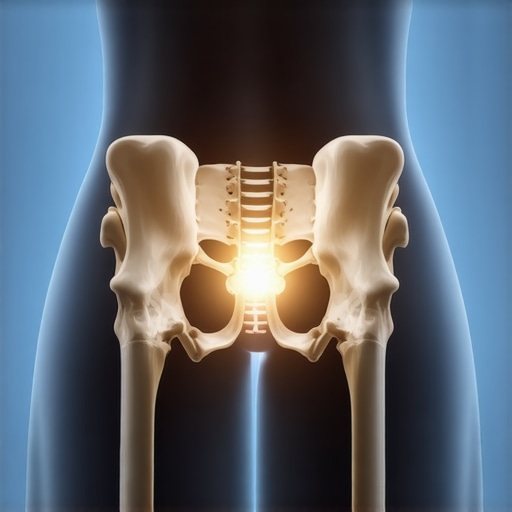

I remember countless mornings waking up feeling like I’d been hit by a truck, my lower back stiff and unyielding, especially around my sacroiliac (SI) joint. No matter how many stretches I did—those popular routines everyone swore by—the pain stubbornly persisted. It was as if my body was telling me, “Nice try, but you’re missing something crucial.” That lightbulb moment changed everything for me.

See, I believed that consistent stretching was enough. I thought if I just rolled out my hamstrings or loosened my hips daily, I’d break free from that relentless SI joint pain. However, I soon realized that this approach is often futile because a locked SI joint isn’t about muscle tightness alone. It’s about joint mechanics and alignment. Relying solely on stretches is like trying to fix a car’s engine by polishing the headlights—you’re missing the root cause.

Early on, I made the mistake of dedicating hours to stretching routines and massage guns, hoping they’d unlock my pelvis. While these can provide temporary relief, they don’t address the vital issue—misalignment that needs a different kind of attention. According to a recent study, spinal adjustments can significantly improve joint function, unlike stretching alone, which often fails to produce lasting results (source).

If you’ve been battling recurring SI joint problems and feel frustrated with the usual stretches, you’re not alone. I found that understanding the importance of proper joint alignment made all the difference. Over the next sections, I’ll share practical strategies that finally helped me move past this stubborn pain and regain my mobility. Ready to learn what actually works? Let’s dive in and tackle this problem head-on.